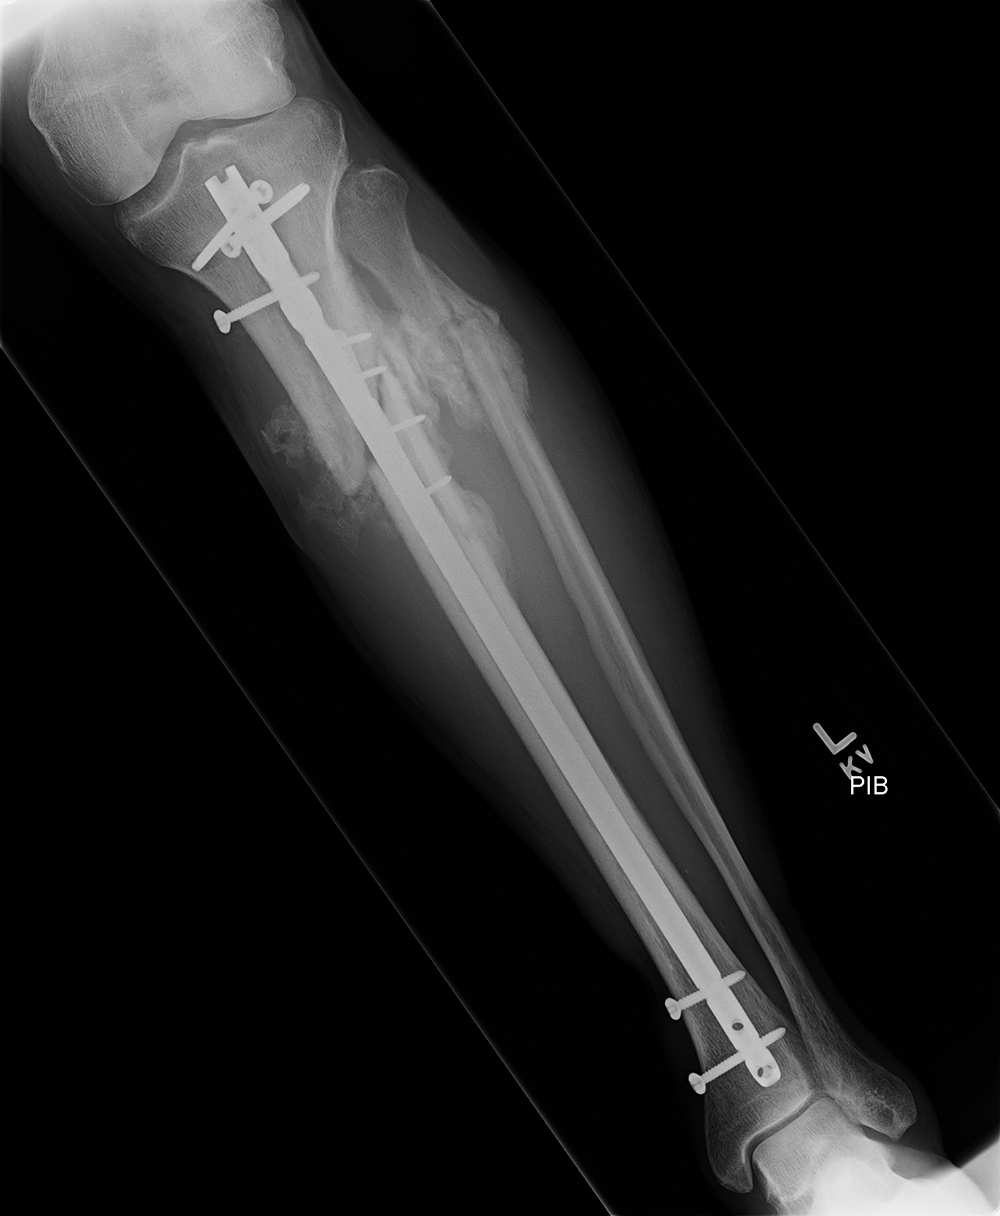

| Male patient with proximal tibia and fibula fractures treated by intramedullary nail and supplemental one-third tubular plate. Initial intraoperative fluoroscopic AP and lateral images (left two images) show the plate (arrow on lateral image). The patient ambulated against advice and was lost to follow-up. Two months later he again presented (right two images) to the clinic. There is now tibia fracture migration, and the proximal medial to lateral interlocking screw has backed out (AP view). The lateral view demonstrates fracture displacement with flexion deformity. The nail has troughed outside the proximal anterior tibia and is sitting within the soft tissues. The supplementary plate is broken, there is a broken interlocking screw, and abundant fracture callus is present. |